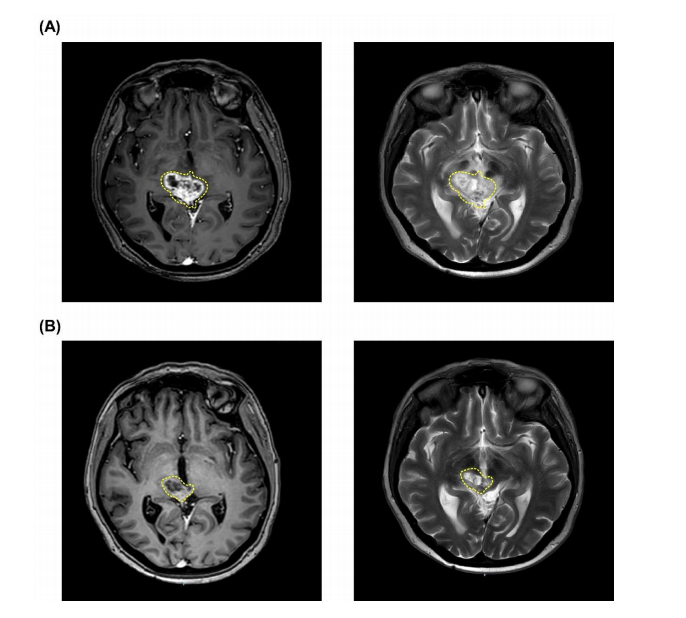

患者為1名6歲男孩,于2020年3月首次出現(xiàn)眼球活動(dòng)受限并伴有明顯的嗜睡。經(jīng)MRI診斷為彌漫性中線膠質(zhì)瘤。2020年3月底,他接受常規(guī)放療(39Gy,13次),并于2020年7月接受化療。后轉(zhuǎn)入臺(tái)北榮總,經(jīng)檢查,腦部影像顯示腫瘤體積為8.77mL,L-BPA攝取研究顯示T/N值為2.45(圖1A)。患者分別于2020年7月17日和2020年8月14日接受兩次BNCT。第一次BNCT治療的平均腫瘤劑量為7.22Gy-E,最小腫瘤劑量為4.19Gy-E,最大腫瘤劑量為11.54Gy-E。在第一次BNCT時(shí),血液中的硼濃度為24.19ppm。第一次BNCT治療1個(gè)月后,18F-BPA-PET顯示,T/N比值下降至2.11(圖1B)。第二次BNCT的平均腫瘤劑量為5.76Gy-E(最小劑量3.38Gy-E,最大劑量9.40Gy-E),血硼濃度為24.62ppm。

圖1:PET和MRI圖像

18F-BPA-PET檢查顯示T/N比為3.83?;颊咴?021年11月、12月共接受兩次BNCT治療。第一次和第二次BNCT的平均腫瘤劑量為10.95 Gy-E和9.68 Gy-E。在第一次和第二次BNCT治療期間,血硼濃度分別保持在22.85ppm和26.95ppm?;颊咴趦纱蜝NCT治療后獲得了CR(圖3),未觀察到嚴(yán)重急性或晚期毒性反應(yīng)。截止到交稿時(shí),患者身體狀況良好,沒有復(fù)發(fā)和進(jìn)展。

圖3:腫瘤縮小的MRI圖像,經(jīng)過兩次BNCT,患者達(dá)到CR,黃色虛線處表示腫瘤。